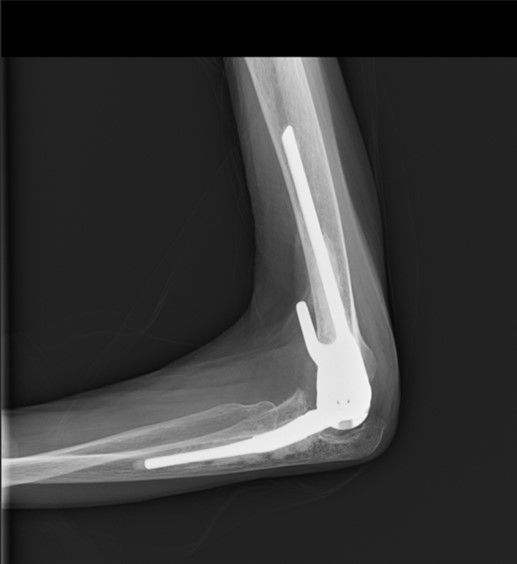

手術療法は大きく分けて人工関節置換術と関節形成術があります。軟骨が消失して変形をきたした関節に対しては人工膝関節、股関節、足関節、肩関節(リバース型を含む)、肘関節、指関節置換術を行っております。当院では感染予防のため最高ランクのクリーンルームで人工関節を行っています。

人工膝関節、人工股関節を行う病院は増加傾向ですが、人工肘関節を行う病院は本邦においてもそれ程多くありません。当科の診療責任医長は模擬骨を用いた人工肘関節の手術手技インストラクターも行っており、経験豊富な医師の下で手術を受けることができます。

下図は連結していない機種を用いた人工肘関節であり、骨切除量が少ない利点があります。